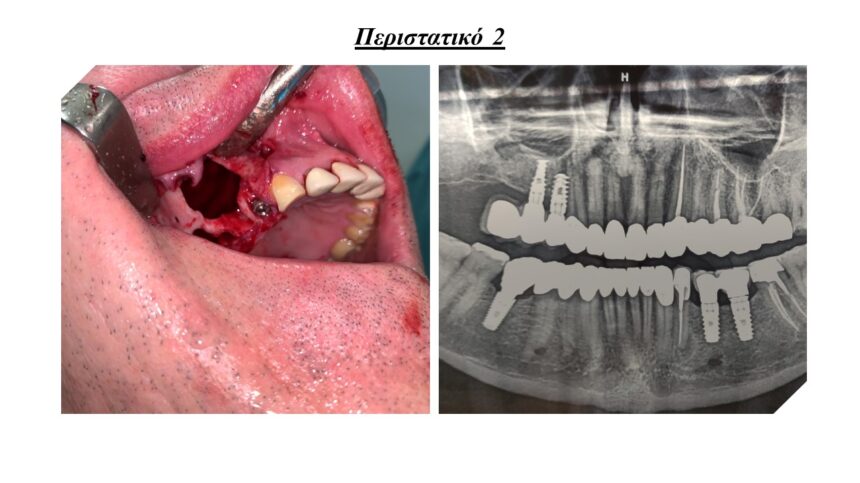

Άμεσα εμφυτεύματα και τεχνικές ώστε να αποφευχθεί η μακροχρόνια απορρόφηση της ακρολοφίας.

Μεταξύ των επεμβάσεων - εφόσον υπάρχει χρόνος - θα παρουσιαστούν περιστατικά, ολοκληρωμένα από 20ετίας, τα οποία θα περιλαμβάνουν όλα τα παραπάνω ( τη χρήση μεμβρανών, PRF και ανύψωση της μεμβράνης ιγμορίου.